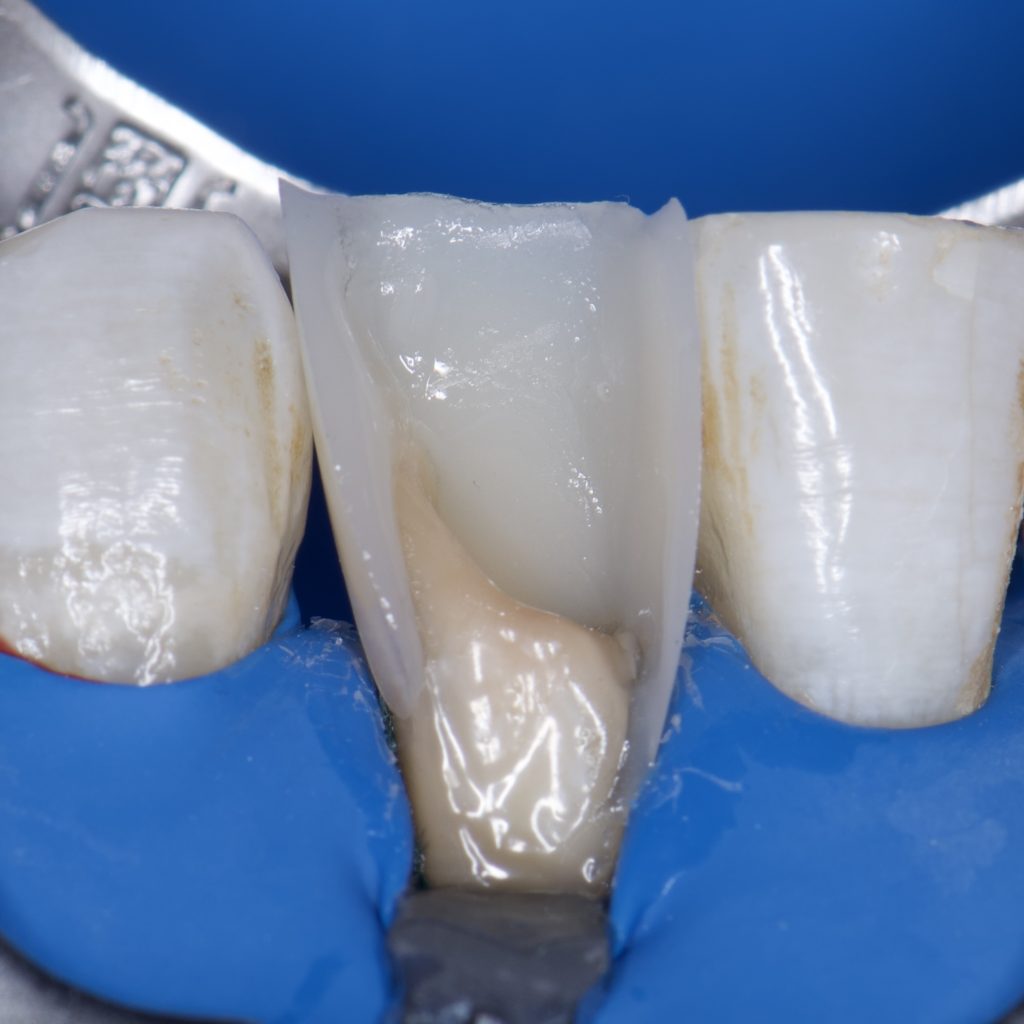

-Isolation with rubber dam

– SE clearfil bond

– Ribbond

– Direct composite restoration, layering technique